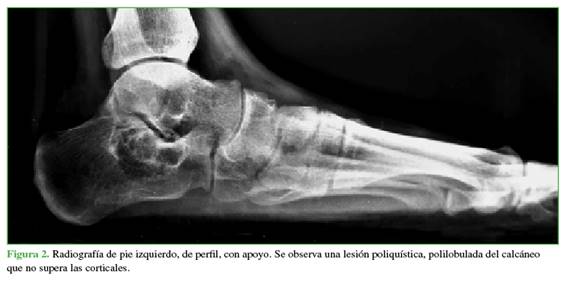

La radiografía de pie, de perfil, con carga muestra una imagen polilobulada, poliquística, que no supera las corticales del calcáneo izquierdo (Figura 2). En la RM sin contraste, se observa una lesión expansiva, excéntrica, de contornos bien definidos, polilobulada, con niveles líquido-líquido en su interior de 3,3 cm anteroposterior, 3,3 cm transversal y 2,7 cm cefalocaudal (Figura 3).